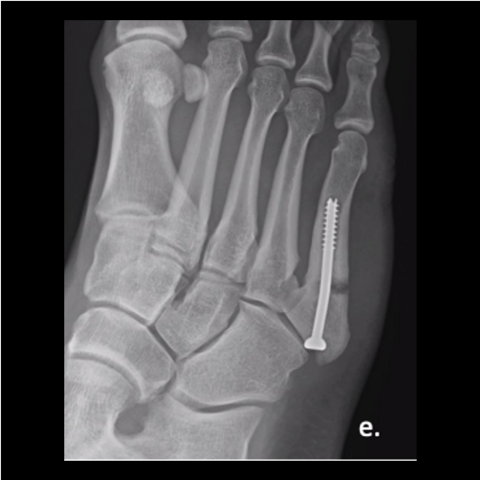

Figure 2b

Figure 2b. A 30-year-old male soldier was injured playing basketball, as shown in this film taken upon injury. We fixated his fracture with a solid screw system. He returned to full duty in 4 months and was pain-free in days after his surgery.